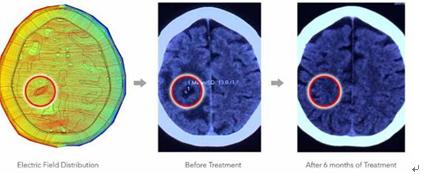

ECCT治疗的过程包含3个步骤:(1)通过MRI或CT定位肿瘤,(2)设计电容电极,计算肿瘤治疗区域内电场分布,(3)根据电场强度分布优化电极设计,使肿瘤细胞获得足够强度的电场,并考虑到与肿瘤位置相连的静脉通道来处理死亡细胞。

电场疗法治疗脑肿瘤的大致过程:计算电场,治疗前后行CT检查。